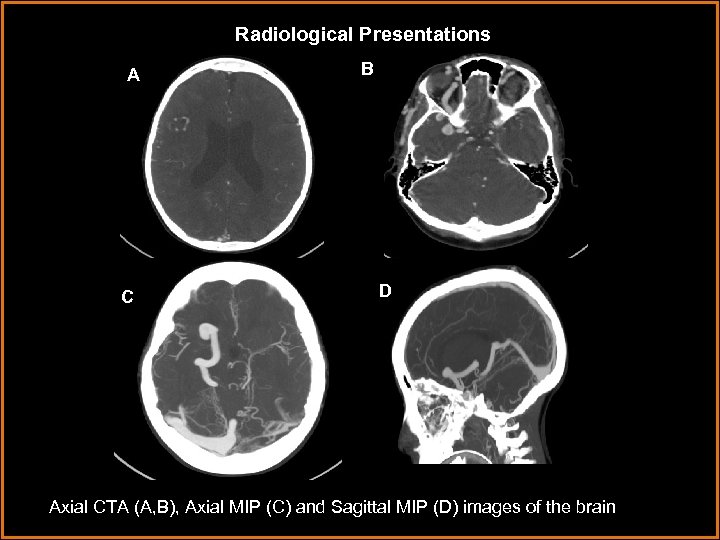

Radiological Presentations A C B D Axial CTA (A, B), Axial MIP (C) and Sagittal MIP (D) images of the brain

Findings A. Axial CTA demonstrates lack of contrast opcification of the torcula with cavernous transformation of the dural sinus with numerous tiny arteriovenous shunts within the dural sinus wall. Cavernous transformation refers to the formation of venous collaterals within or around a chronically thrombosed venous structure. Cavernous transformation is alternately referred to as formation of a “venous recipient pouch” A B. Axial MIP demonstrates cavernous transformation and thrombosis of the left transverse sinus with numerous tiny arteriovenous shunts within the sinus wall (◄), arterial feeder entering the right transverse sinus (→) and dilated basal vein of Rosenthal (→). → B • Normally, venous drainage proceeds through bilateral transverse sinuses, inferiorly to the sigmoid sinuses through the jugular veins. → → ◄ • In this case, there is thrombosis of both sigmoid sinuses, the left transverse sinus and anterior two thirds of the superior sagittal sinus. Thus, the normal pathways of venous drainage are occluded and so venous drainage is accomplished by draining in an anterior retrograde fashion through the strait sinus → vein of Galen → basal vein of Rosenthal → inferior ophthalmic vein → facial veins. • Additionally there is arterial input to the right transverse sinus resulting in venous hypertension and dilatation.

Findings A. Axial CTA demonstrates enlargement of the inferior ophthalmic vein secondary to retrograde venous drainage and venous hypertension A ► B G R S A. Sagittal MIP demonstrates retrograde venous drainage anteriorly through enlarged strait sinus (S)→ vein of Galen (G)→basal vein of Rosenthal (R)→ inferior ophthalmic vein→ facial veins. There is significant dilatation of these venous structures indicating venous hypertension.